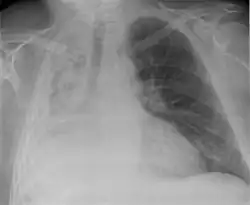

Left tension pneumothorax with a large, well-demarcated area devoid of lung markings with tracheal deviation and movement of the heart away from the affected side.

Tension pneumothorax

Tension pneumothorax is an emergent condition in which air gets trapped in the space between the chest wall and the lung. This space is referred to as the pleural space. Because air can't escape from this space, the air pocket grows larger and larger, resulting in the lung collapse closest to the pneumothorax. Forces are transmitted to the mediastinum and effectively "push" the mediastinal structures to the opposite side of the chest.[5]